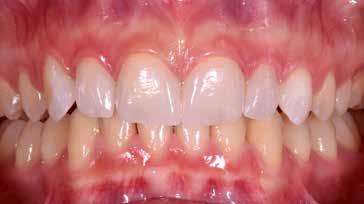

97 96 ESTETICA FUNZIONE POSTURA 145 _ Profilo sinistro con sorriso. 146 _ Ripresa di 3/4 sinistra con sorriso. 147 _ Immagine frontale naturale, senza sorriso. 148 _ Immagine frontale con sorriso. 149 _ Ripresa di 3/4 destra con sorriso. 150 _ Profilo destro (senza) con sorriso. 151 _ Dettaglio del sorriso. 152 _ Dettaglio del sorriso nel profilo destro. 153 _ Dettaglio del sorriso nel profilo sinistro.